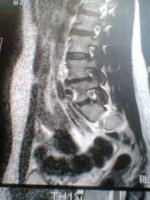

ich versuch es einfach mal...also ich hab seit ca 2 Jahren einen Bsv L4/L5 bislang ohne OP...

ich war 4 Wochen in reha danach habe ich die Wiedereingliederung gemacht und arbeite seitdem wieder in Vollzeit ( seit September 2011 ) jetzt seit 1 Monat habe ich wieder starke schmerzen und dazu gekommen ist mein Steißbein,kann kaum sitzen und beim aufstehen tut es höllisch weh

arbeiten geh ich zur zeit nur 5-7 Std danach geht nicht mehr.....nehme seit ca 7 Monaten Targin 20mg/10 mg 3 mal am Tag...so wirklich lange helfen die leider auch nicht mehr...Heute war ich beim MRT könnte jemand von euch mir die ein bissel beschreiben????